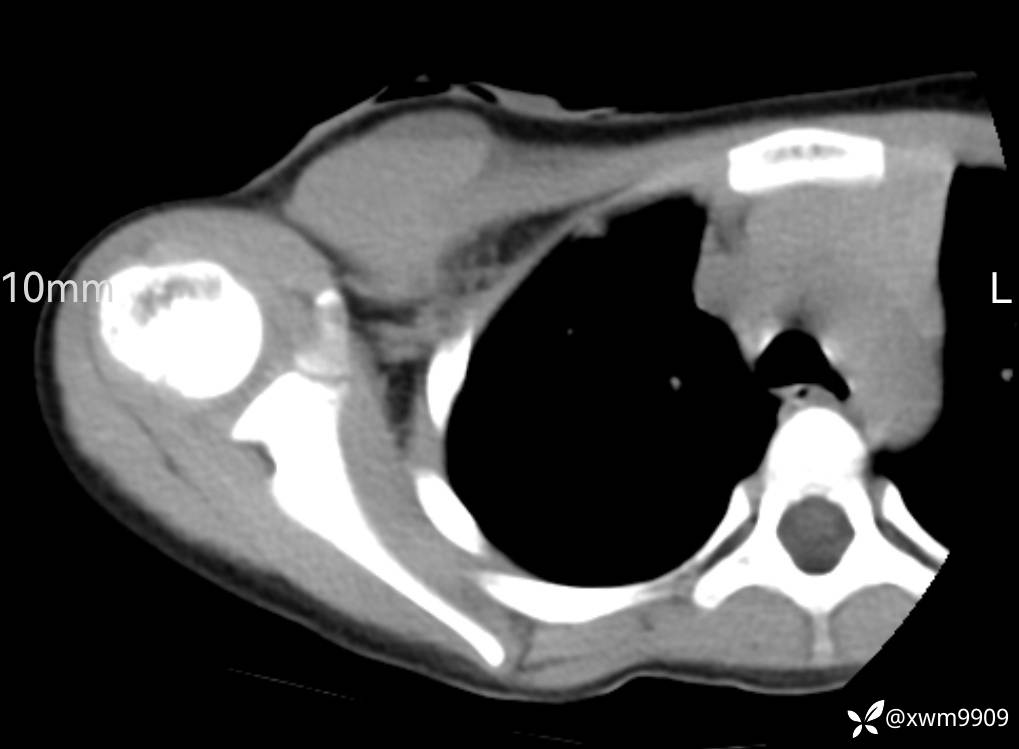

CT:

3、查体,右锁下方可及一约5x6Cm肿物,软丶边清丶未见明显发红,肤温不高,压痛明显,不可推动,稍有波动感。其他无特殊。

2024-03-20,女,6岁。因“发现右侧胸部肿物伴疼痛1天”入院。